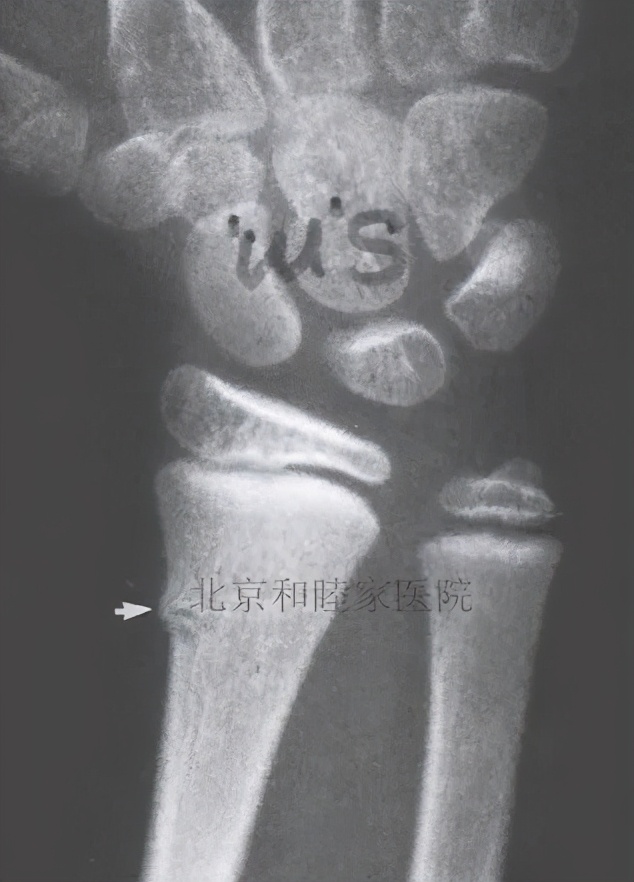

骨骺损伤(Epiphyseal injuries):

骨骺损伤是指儿童特有的骨结构——生长板受损。

温馨提示: 生长板 是在骨头两端存在的特殊结构,闭合后骨头就会停止生长,因此这个结构的存在 与家长们普遍非常关心的“孩子能长多高”有很大关系 , 对于身高其他的影响因素还有遗传、营养以及运动 。